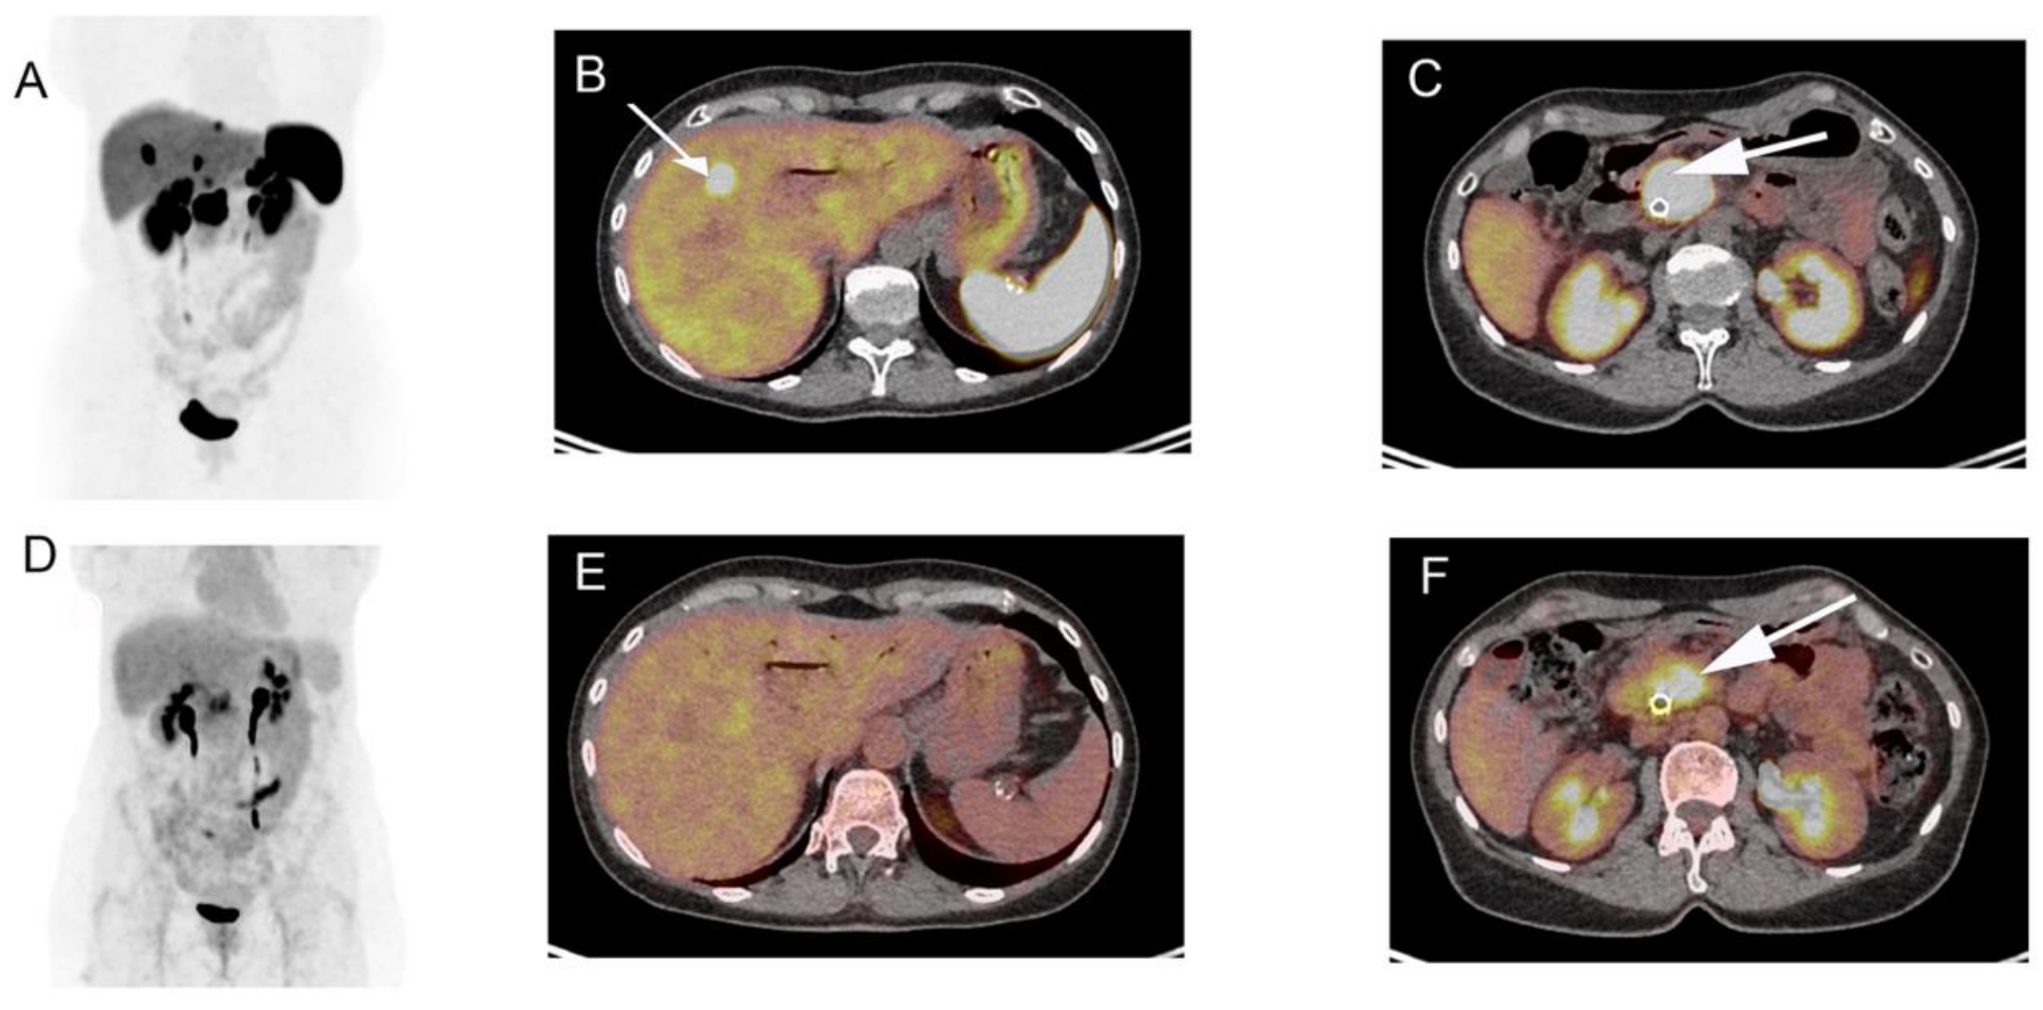

3.1. Functional Imaging

- Hindié, E. The NETPET score: Combining FDG and somatostatin receptor imaging for optimal management of patients with metastatic well-differentiated neuroendocrine tumors. Theranostics 2017, 7, 1159–1163. [Google Scholar] [CrossRef]

- Chan, D.L.; Pavlakis, N.; Schembri, G.P.; Bernard, E.J.; Hsiao, E.; Hayes, A.; Barnes, T.; Diakos, C.; Khasraw, M.; Samra, J.; et al. Dual somatostatin receptor/FDG PET/CT imaging in metastatic neuroendocrine tumours: Proposal for a novel grading scheme with prognostic significance. Theranostics 2017, 7, 1149–1158. [Google Scholar] [CrossRef]

- Zhang, P.; Yu, J.; Li, J.; Shen, L.; Li, N.; Zhu, H.; Zhai, S.; Zhang, Y.; Yang, Z.; Lu, M. Clinical and prognostic value of PET/CT imaging with combination of 68Ga-DOTATATE and 18F-FDG in gastroenteropancreatic neuroendocrine neoplasms. Contrast Media Mol. Imaging 2018, 2018, 2340389. [Google Scholar] [CrossRef]